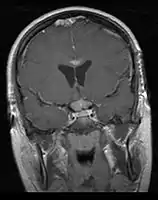

CNS Germinoma

- Mainly located in midline structures, suprasellar region or pineal gland, also basal ganglia and hypothalamus

Location

- Pineal Gland Germinoma

- Suprasellar Germinoma